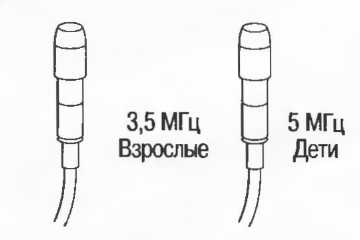

Затухание

Ткани тела поглощают и рассеивают ультразвук по-разному. Высокие частоты поглощаются и рассеиваются (гасятся) в большей степени, чем низкие. Поэтому, чтобы достичь более глубоких тканей, необходимо использовать более низкие частоты, так как менее вероятно, что эти волны затеряются при прохонодении через ткани. На практике оптимально использовать частоту около 3,5 МГц для глубокого сканирования у взрослых и частоту 5 МГц и выше для исследования более худых пациентов или детей. Частота 5 МГц и выше используется для исследования поверхностных органов у взрослых.

Выбор соответствующего датчика

Наилучшим датчиком для общей практики является конвексный датчик с частотой 3,5 МГц с фокусировкой на расстоянии 7-9 см. Если такого датчика нет, необходимо наличие линейного секторного датчика с частотой 3,5 МГц. При необходимости исследования детей и худых взрослых желательно дополнить набор датчиком с частотой 5 МГц с фокусировкой 5-7 см.

1. Ультразвуковые исследования в акушерстве. Для общих исследований в акушерстве используется линейный или конвексный датчик с частотой 3,5 или 5 МГц с глубиной фокусировки на 7-9 см. Если закупается только один датчик, выбирайте датчик с частотой 3,5 МГц. Датчик с частотой 5 МГц предпочтителен на ранних сроках беременности. В поздние сроки беременности лучше использовать датчик с частотой 3,5 МГц.

2. Ультразвуковые исследования в общей практике. Если проводятся исследования в верхней части живота и таза у взрослых, в том числе и акушерские исследования, предпочтительнее выбор секторного или конвексного датчиков с частотой 3,5 МГц с глубиной фокусировки на 7-9 см.

3. Ультразвуковые исследования в педиатрии. Для детей необходим датчик с частотой 5 МГц с глубиной фокусировки на 5-7 см. При исследовании мозга новорожденного используется секторный датчик с частотой 7,5 МГц с глубиной фокусировки на 4-5 см (этот датчик также используется для исследования яичек и структур шеи у взрослых).